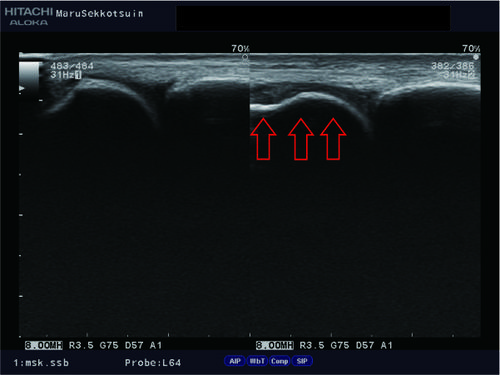

昨日はサッカー中に相手と接触し膝を痛めた方。

内側側副靭帯、内側半月板、前十字靭帯の損傷疑い。

triad2.jpg

この複合損傷は「unhappy triad:不幸の三徴候」と言われ、

膝の構造上、同時に損傷する場合があります。

こちらの患者さんもその兆候が見られ、

しっかりとフォロー&ケア。